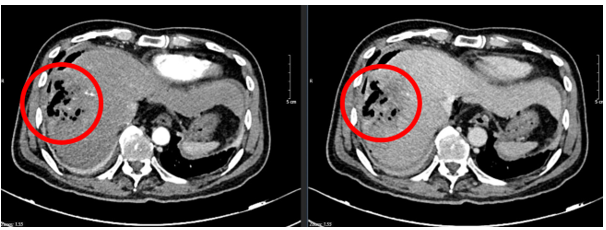

– Chụp cắt lớp vi tính ổ bụng:

Hình 1: Hình ảnh chụp cắt lớp vi tính ổ bụng: Nhu mô hạ phân thùy S7-8 có khối (vòng tròn đỏ) tỷ trọng hỗn hợp kích thước 81x51mm gồm phần tăng tỷ trọng của vật liệu can thiệp và nhiều bóng khí tạo thành ổ tụ khí trong nhu mô kèm phần hoại tử dạng dịch, không có huyết khồi.